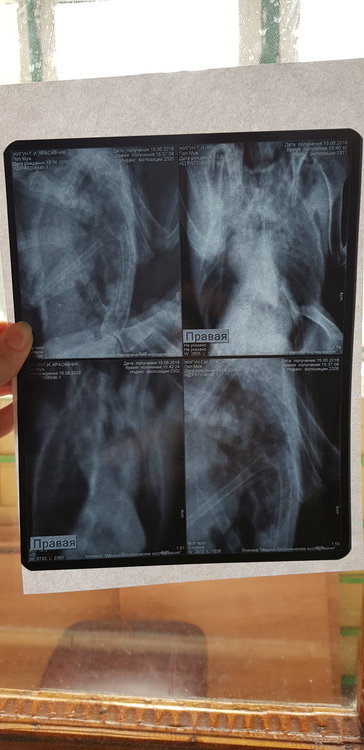

Сделала рентген. Но я в нем не разбираюсь.  Есть ли там грибы в легких. 3 дня по чуть-чуть совсем так чтобы выходило примерно 5 по на день орунгамин. И сейчас ему совсем плохо. Один глаз закрыт, помутнеет. Постоянно пытается отрыгнуть или делает такие движения. Совсем вялый. Фото прикреплю в сообщении ниже